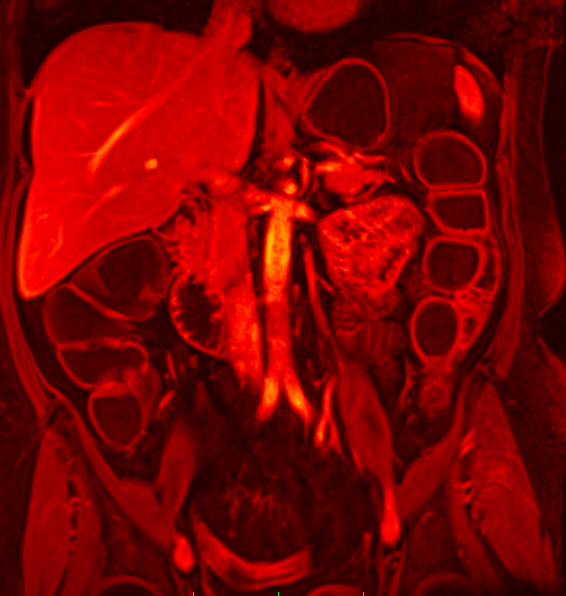

Zu den eingesetzten bildgebenden Methoden gehören neben dem Röntgen vor allem moderne Schnittbildverfahren wie die strahlenfreie Magnetresonanztomographie (MRT), die Computertomographie (CT) und der Ultraschall (Sonographie). Die Abteilung für Radiologie am AKH Celle verfügt über eine hochmoderne radiologische Geräteausstattung, die unter anderem eine routinemäßige Durchführung von radiologischen Spezialuntersuchungen wie die Untersuchung des Herzens oder der Prostata ermöglicht.

Magnetresonanztomographie: Gesamtes Spektrum der MRT-Diagnostik

- MRT Diagnostik des Halses, Brustkorbes, Bauchraumes und Beckens

- MR Angiographie des gesamten Gefäßsystems

- Ganzkörper MRT